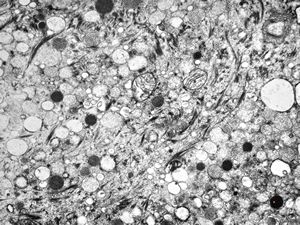

M, 63y. | suprarenal neuroblastoma

M, 3y. | suprarenal neuroblastoma